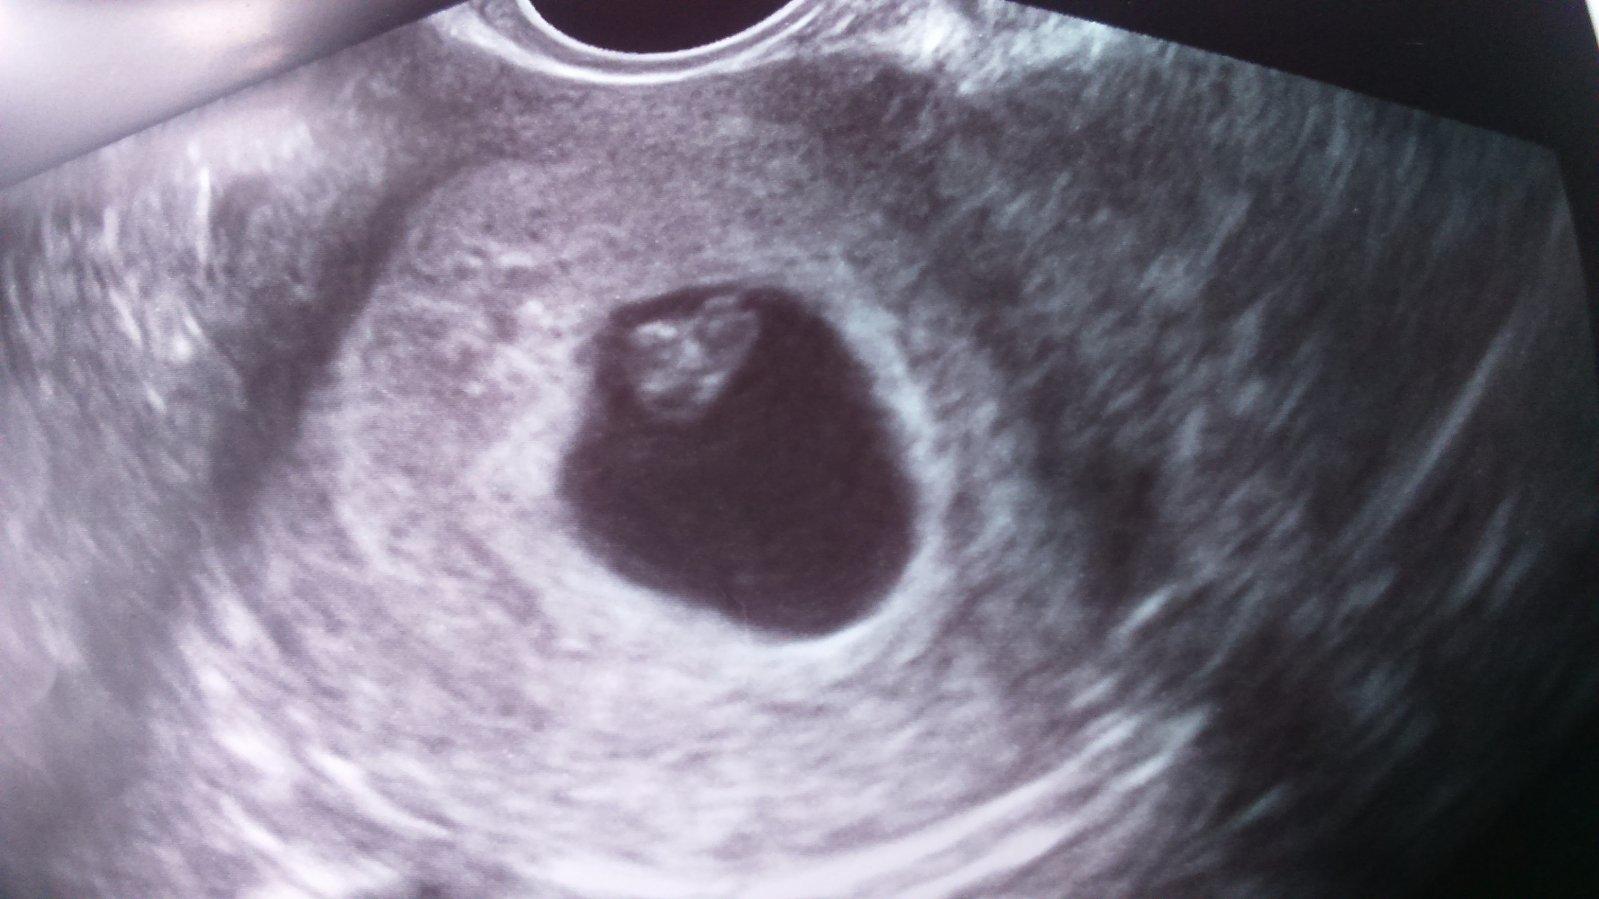

Tak dievčatá moje.predstavujem vám naše ❤ som 6+6 A zodpovedá 6+2tt. Čiže super,termín pôrodu mám 20.12. Srdiečko krásne bilo 🙂 až som podskocila na tej koze keď mi ukázala monitor. Ďalšia kontrola 30.5.uz bude knižka+ odbery.no sa asi nedospim. Veľmi sa teším. Teším sa na vaše dobre správy nech sa môžeme všetky spolu tešiť 😘